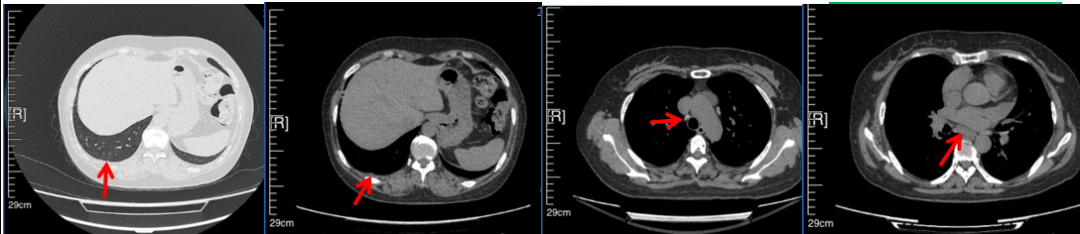

2016年1月复查CT提示支气管截断可见新发小结节,一线治疗采用培美曲塞+DDP方案化疗4周期(培美曲塞3.36,DDP 480mg)。化疗后复查胸部CT:右肺见不规则结节样影,最大层面大小约19mm*8mm,较前比较明显增大,疗效评估PD。2017.3-2017.4予单药多西他赛化疗3周期,疗效评估SD。2018年5月末复查CT提示结节较前增大,评效为PD,2018年6-10月予多西他赛+CBP化疗4周期,疗效评估SD。2022年5月患者出现活动后气短,复查胸部CT示右肺膨胀不良;右侧胸腔积液增多。胸腔积液包埋病理示符合肺腺癌细胞。行NGS基因检测:EML4:exon13-ALK:exon20融合。PD-L1(克隆号22C3)TPS<1%。

2018.07

2022.05